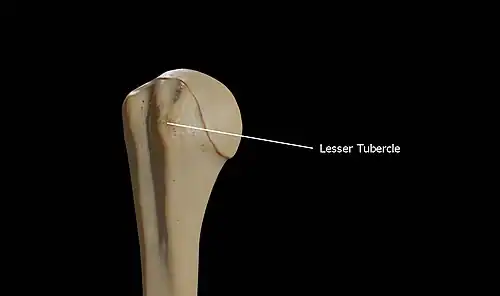

Lesser tubercle

The lesser tubercle of the humerus, although smaller, is more prominent than the greater tubercle: it is situated in front, and is directed medially and anteriorly.

The projection of the lesser tubercle is anterior from the junction that is found between the anatomical neck and the shaft of the humerus and easily identified due to the intertubercular sulcus (Bicipital groove).